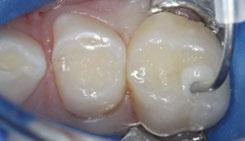

The 5-year-old patient featured in this case study did not benefit from early oral care and had multiple carious lesions. Considering the young age, high caries risk, and the uncertainty of compliance with follow-up appointments, I wanted to restore and seal all teeth in one visit. One quadrant is shown in this case study. The carious lesion on tooth J (65) was cavitated and prepared, restored, and sealed. Tooth I (64) was non-carious and would only be sealed (Figure 1).

surface of tooth I (64) was also lightly abraded with a diamond bur (Figure 2). The preparations were selectively etched with phosphoric acid, rinsed, and lightly dried (Figure 3). Bonding agent was applied to the entire occlusal surfaces of both teeth, air thinned, and light-cured (Figure 4).

Figure 1 (left): Caries lesion on tooth J (65). Figure 2 (center): Preparation of tooth J (65) and abraded occlusal surface of tooth I (64). Figure 3 (right): Selective etch of enamel Figure 4 (left): Bonding agent is applied to both teeth I and J (64 and 65). Figure 5 (right): The preparation is filled with ACTIVA Kids Figure 6 (left): A thin topcoat of ACTIVA Presto is applied to the occlusal surfaces of teeth I and J (64, 65). Figure 7 (right): Final result